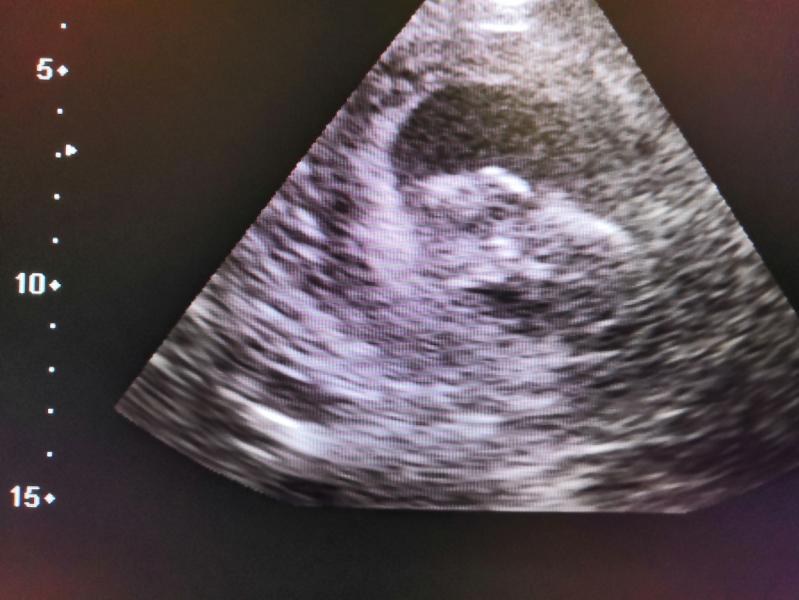

Все, теперь я спокойна до понедельника) В пн 1 скрининг. Была со старшей на узи сердца, попросила глянуть есть ли сердцебиение у ляльки, Слава Богу есть) Можно выдохнуть. Быстренько сфоткала)